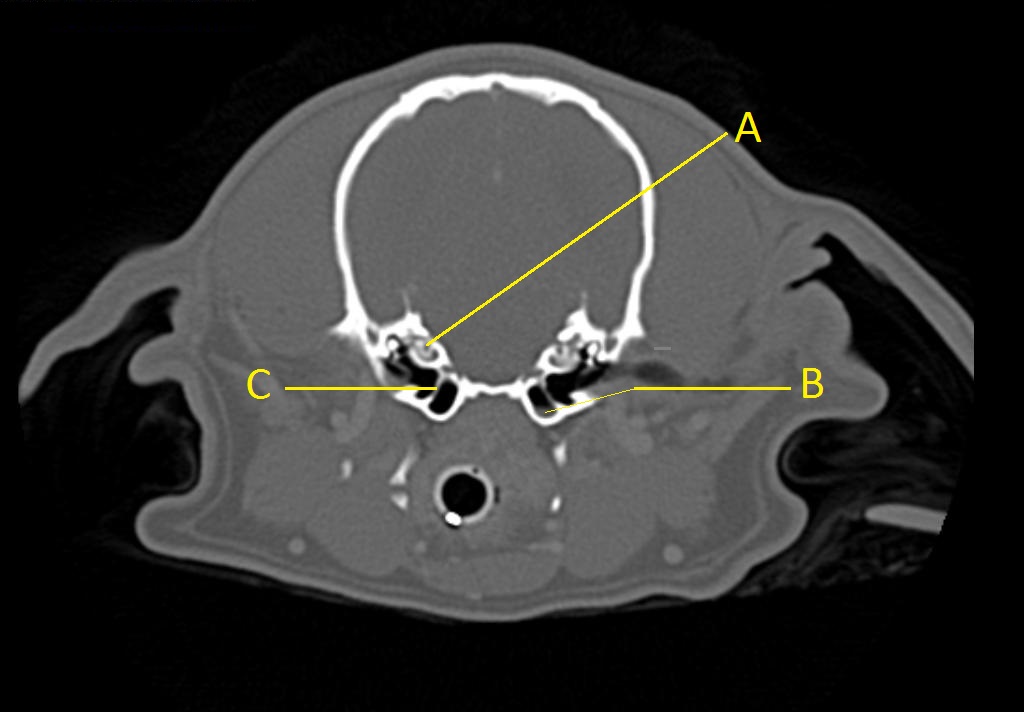

Q. Identify the structures labeled below:

A.

A. cochlea

B. tympanic membrane

C. small amount of fluid in the tympanic bulla